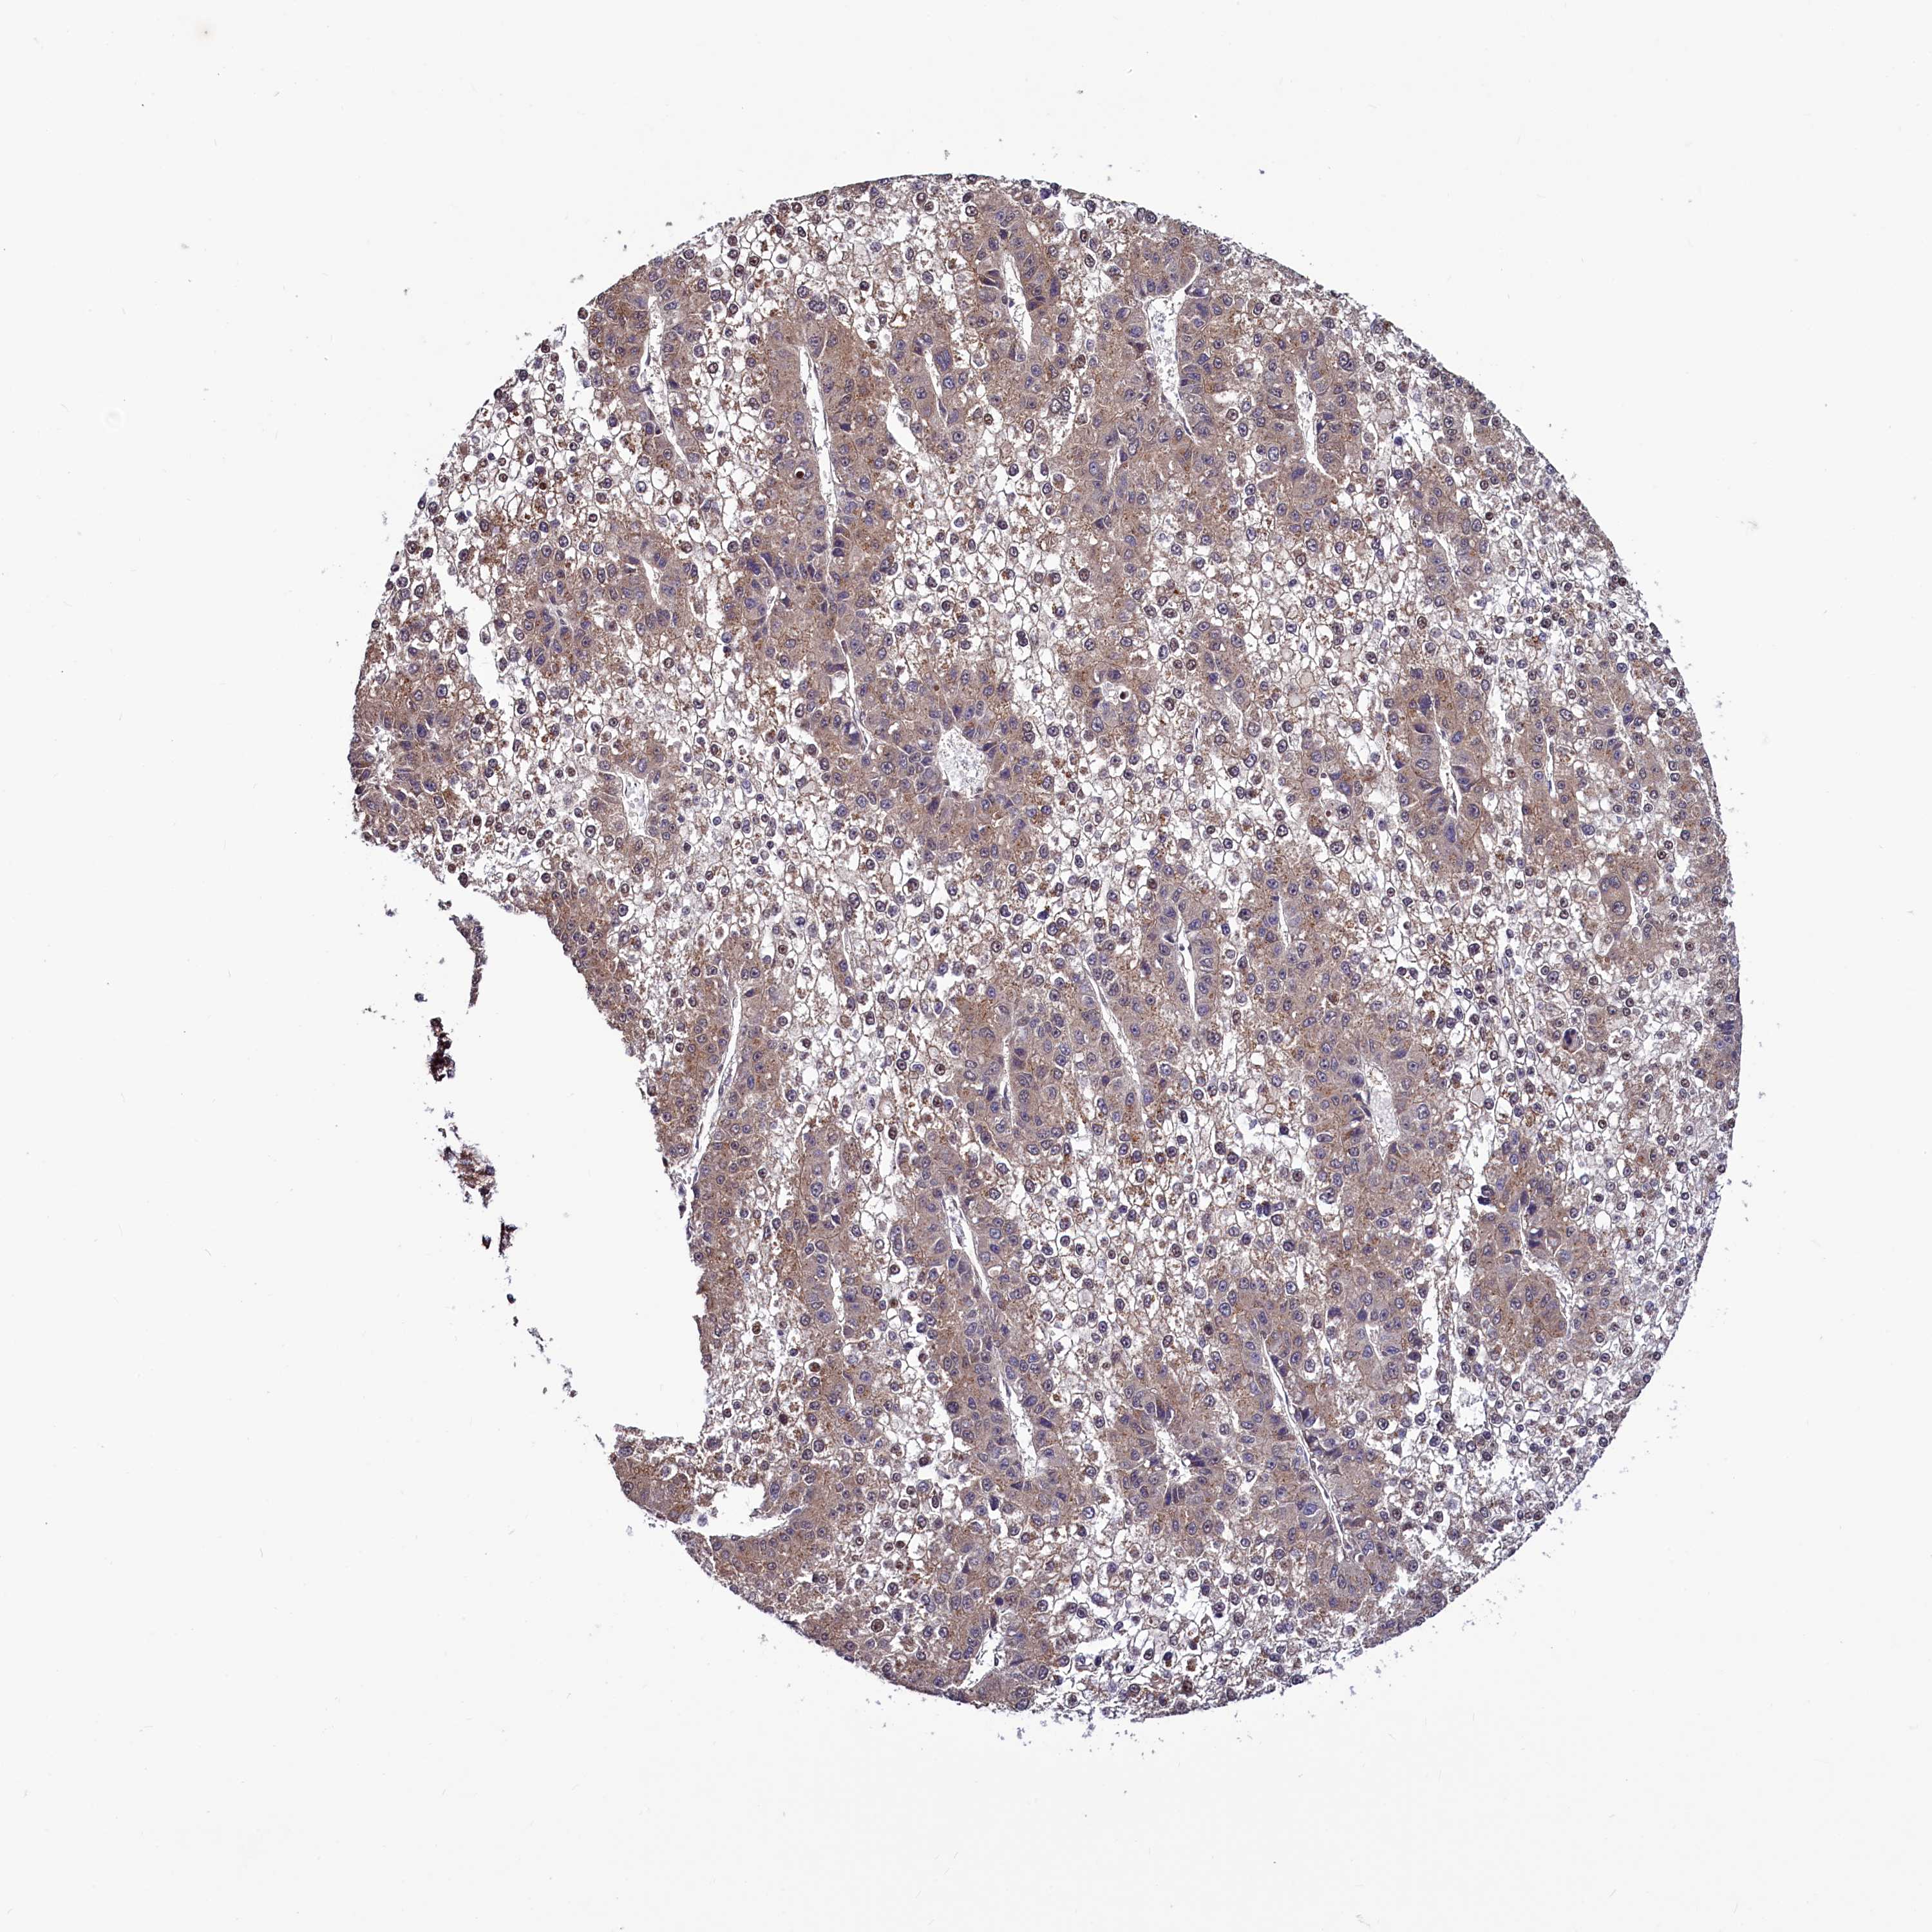

LIVER CANCER - Protein expressioni

A mouse-over function shows sample information and annotation data. Click on an image to view it in a full screen mode. Samples can be filtered based on level of antibody staining by selecting one or several of the following categories: high, medium, low and not detected. The assay and annotation is described here.

Note that samples used for immunohistochemistry by the Human Protein Atlas do not correspond to samples in the TCGA dataset.

Antibody stainingi

Antibody staining in the annotated cell types in the current human tissue is reported as not detected, low, medium, or high, based on conventional immunohistochemistry profiling in selected tissues. This score is based on the combination of the staining intensity and fraction of stained cells.

Each image is clickable and will lead to virtual microscopy that enables deeper exploration of all samples and also displays staining intensity scores, fraction scores and subcellular localization as well as patient and tissue information for each sample.

Antibody HPA040196

Antibody HPA040213

Staining

High

Medium

Low

Not detected

Intensity

Strong

Moderate

Weak

Negative

Quantity

>75%

75%-25%

<25%

None

Location

Nuclear

Cytoplasmic/membranous

Cytoplasmic/membranous,nuclear

Cholangiocarcinoma

Carcinoma, Hepatocellular, NOS